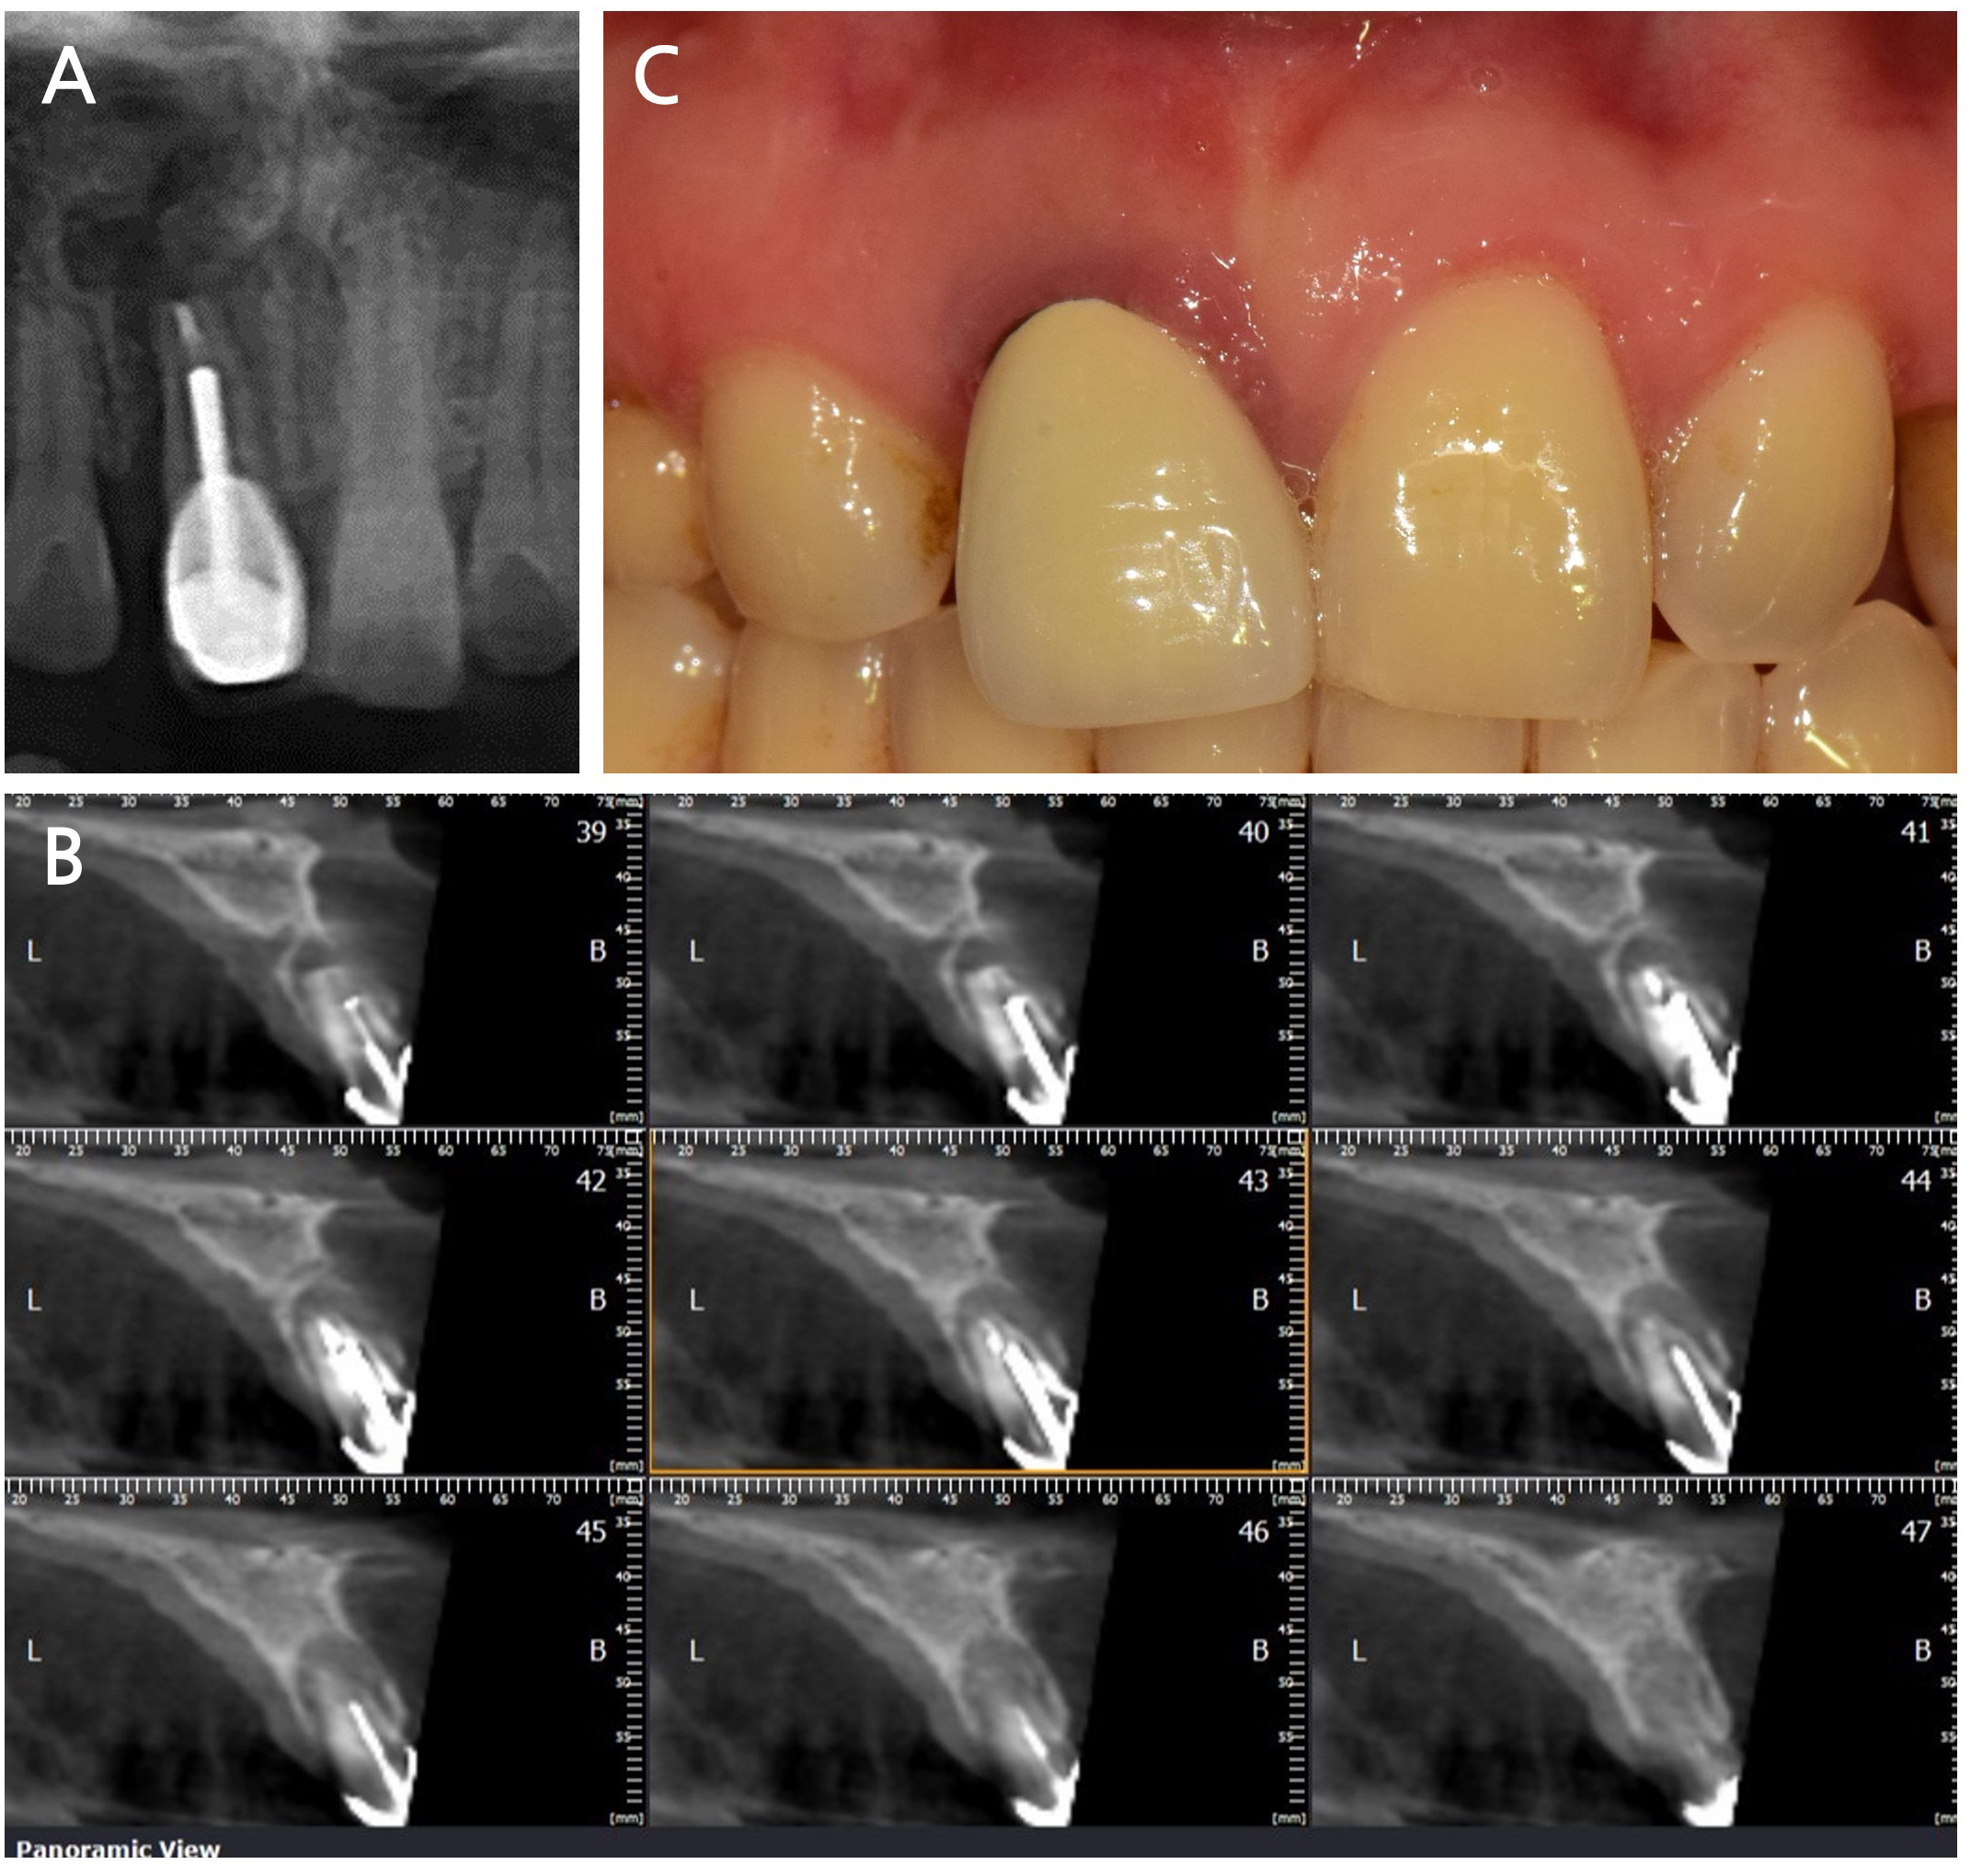

A 42-year-old female patient with no relevant medical history presented to a dental clinic in 2023 with a chief complaint of increased mobility of the maxillary anterior tooth. Radiographic and clinical examinations revealed advanced alveolar bone loss around tooth #11, with particularly pronounced loss in the labial aspect of the socket (Fig. 2). After a comprehensive evaluation, ARP via the intrasocket granulation tissue repositioning technique was planned for the extraction site, followed by delayed implant placement.

Fig. 2

Initial clinical and radiographic findings. (A) Periapical radiograph and (B) cone-beam computed tomography images revealing advanced bone loss on the labial aspect of tooth #11, (C) A clinical photograph showing inflamed, reddish gingiva around tooth #11, indicating localized periodontal inflammation.